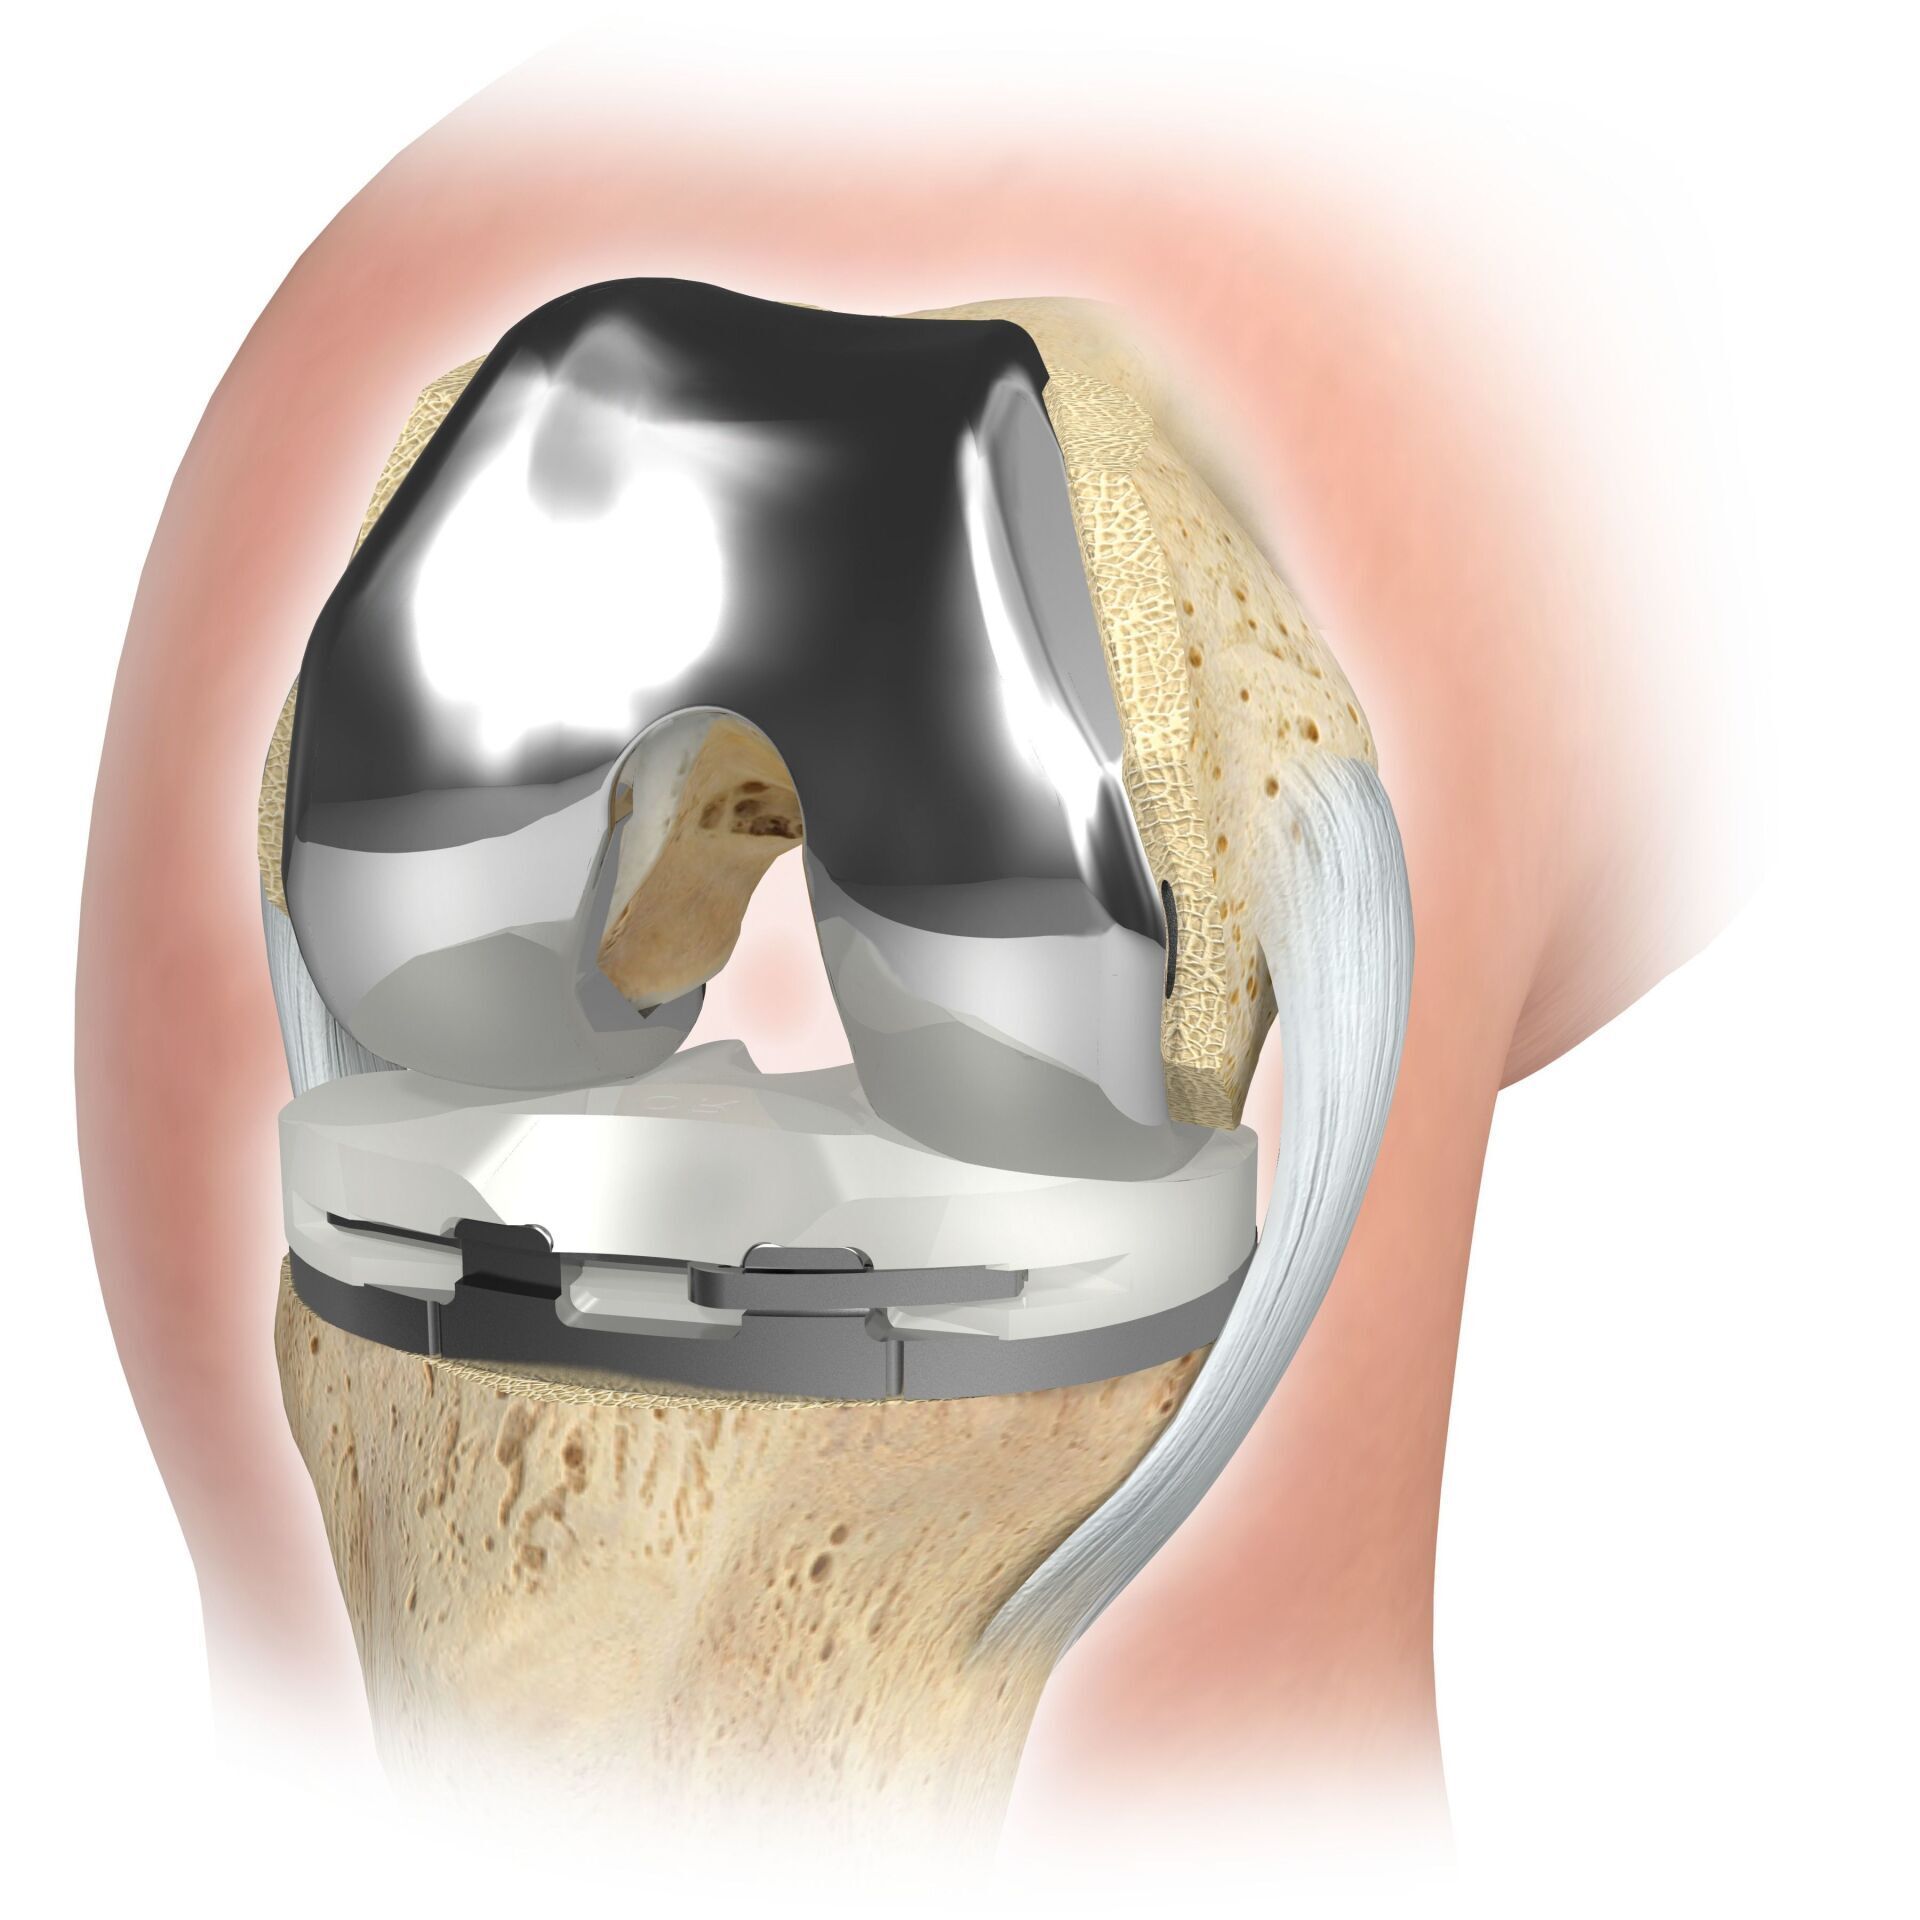

KNEE REPLACEMENT (ARTIFICIAL KNEE JOINT)

The artificial knee joint replaces the cartilage surface destroyed by arthrosis. The underlying bone on the thigh and tibial head remains intact. Some people compare a modern artificial knee joint to a crown on a tooth; the exact term is the so-called bicondylar surface replacement. Between the new surfaces on the thigh and lower leg is the so-called inlay made of a specially hardened white plastic, which can be seen in the X-ray image as the gap between the metal parts.